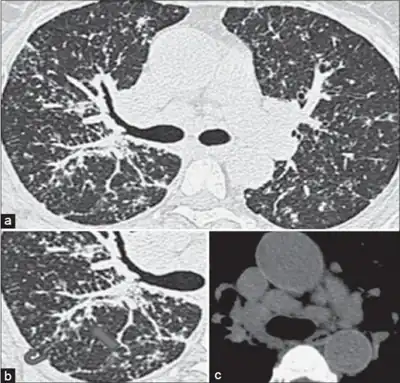

Chest radiography findings of berylliosis are non-specific. Early in the disease radiography findings are usually normal. In later stages interstitial fibrosis, pleural irregularities, hilar lymphadenopathy and ground-glass opacities have been reported.[16][17] Findings on CT are also not specific to berylliosis. Findings that are common in CT scans of people with berylliosis include parenchymal nodules in early stages. One study found that ground-glass opacities were more commonly seen on CT scan in berylliosis than in sarcoidosis. In later stages hilar lymphadenopathy, interstitial pulmonary fibrosis and pleural thickening.[17]